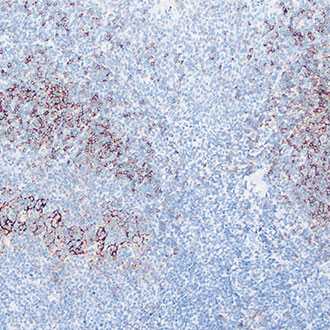

Ki-67

Ki-67 -